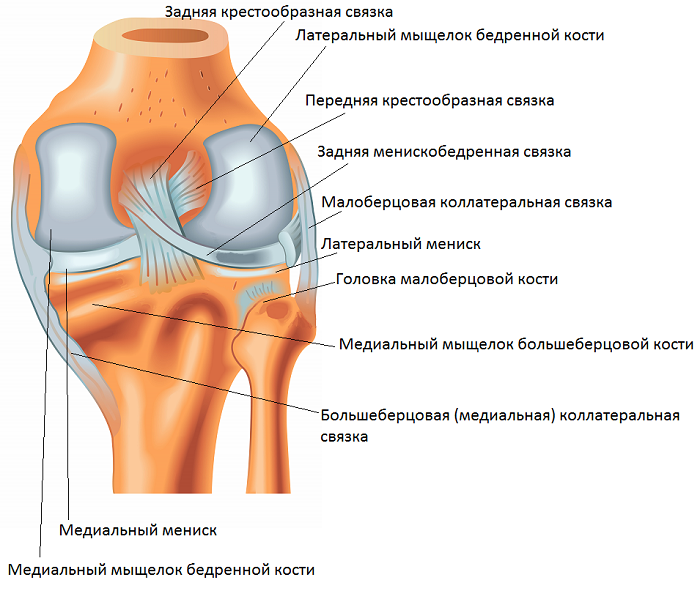

Анатомические изображения менисков и коленного сустава

Раздел: Иллюстрированные советы